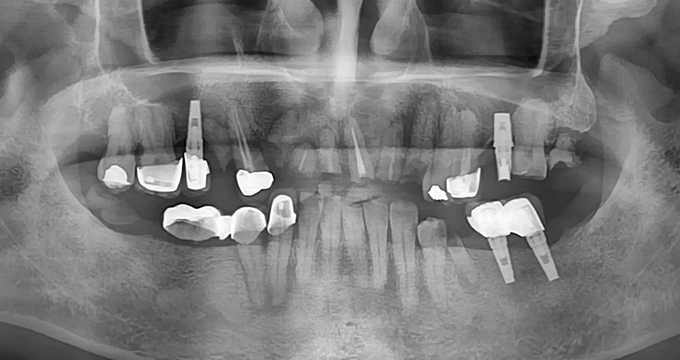

치료 전

40대 남성 환자분으로, 위 아래 치아들이 전체적으로 망가짐에 따라 얼굴의 '수직고경'이라고 하는 하안면의 높이가 줄어들어 있었습니다.

이러한 경우에 당일 1시간 내외의 검진과 상담으로 급하게 치료 결정를 하기보다 다음 내원까지 어떤 치아를 어떤 치료로 살릴지, 빼야만 하는지, 빼고 나서는 어떤 순서로 치료하는지 신중하게 치료 계획 세운 후 여러 단계를 걸쳐 치료를 진행하였습니다.